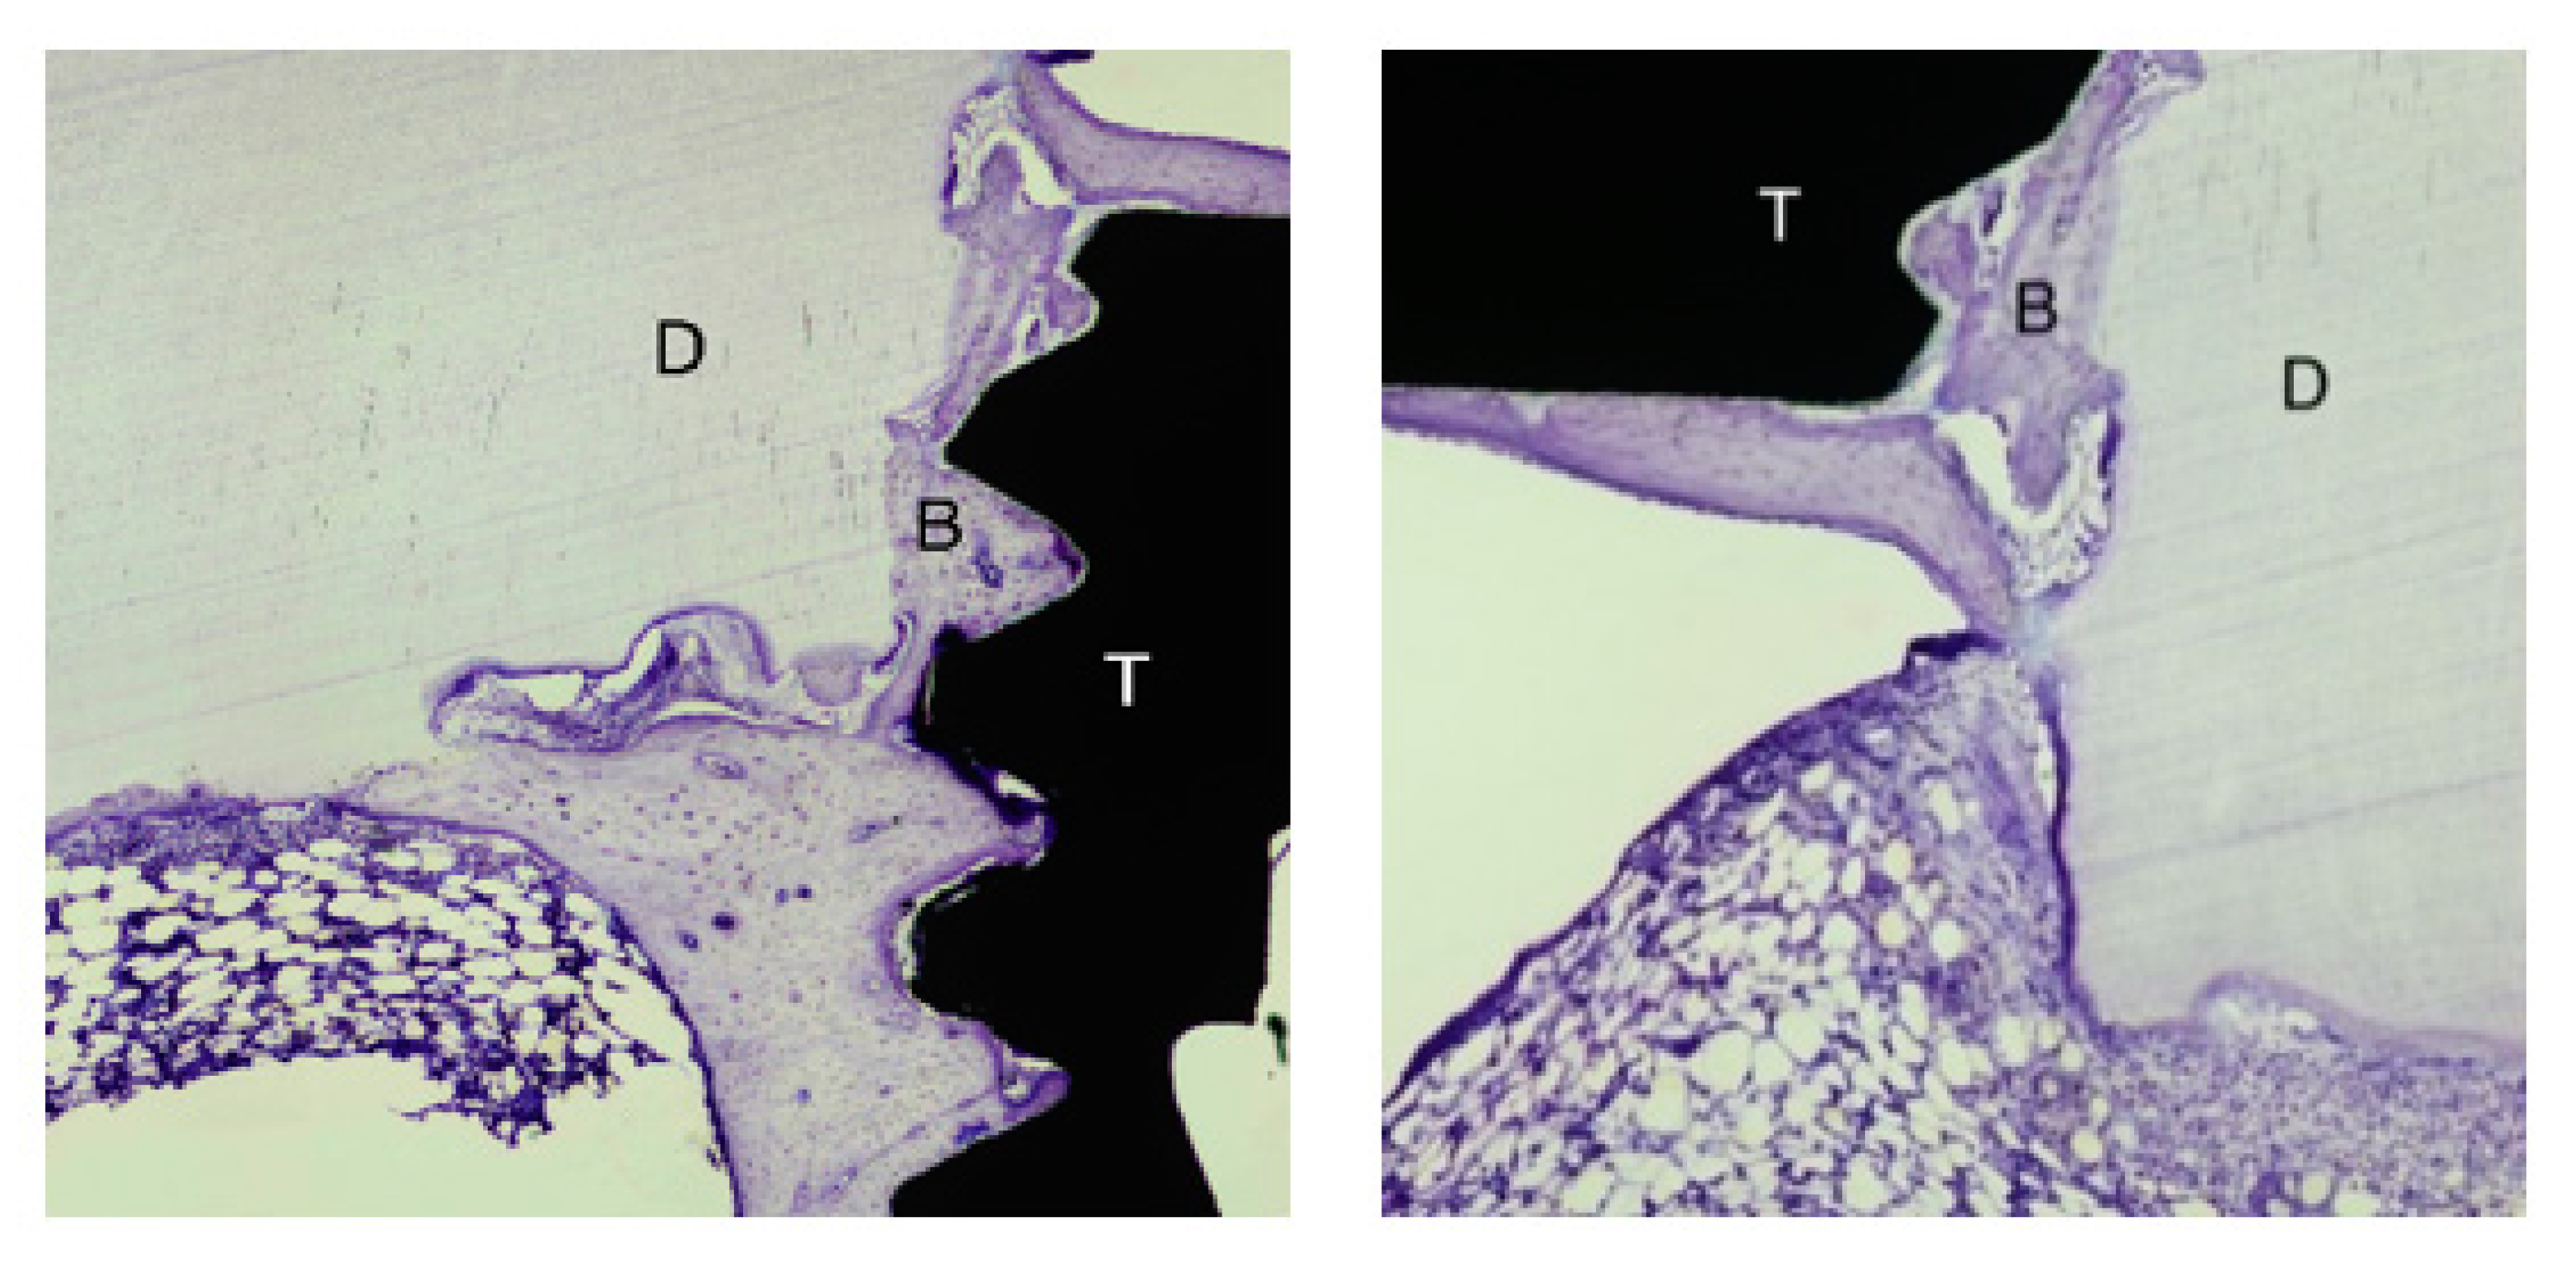

3.1. Descriptive Characterization of Dentin Block

3.2. Bone Healing